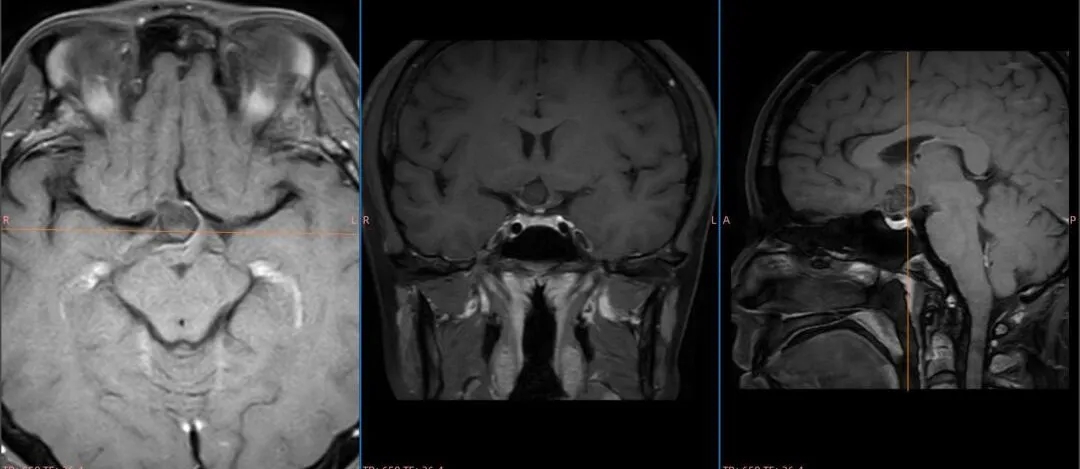

术前影像